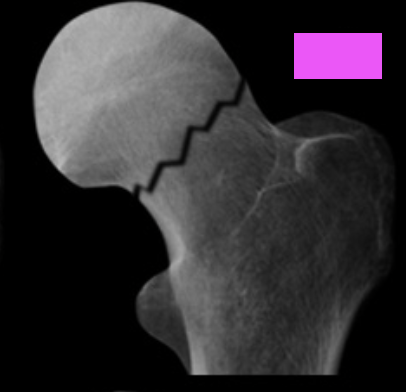

Intracapsular fracture - Subcapital - AP:

Which type of Garden classification is shown [1]

I - Incomplete or impacted bone injury with valgus angulation of the distal component